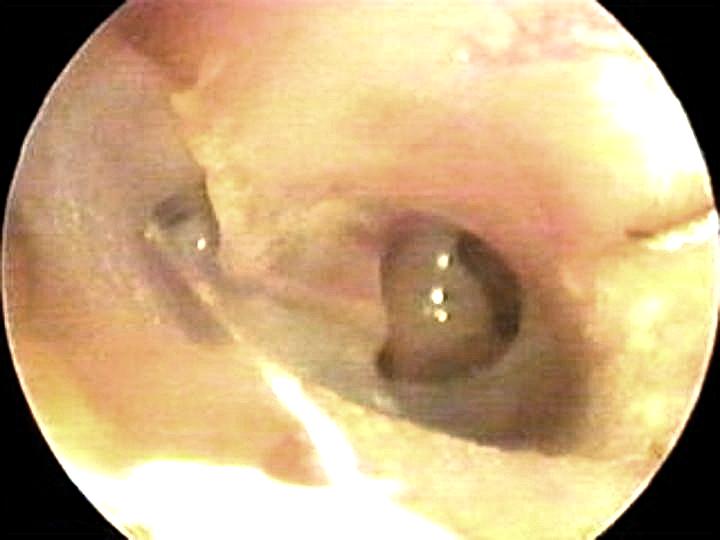

Atelectasia en tímpano izquierdo (bullas en caja timpánica)

Atelectasia en tímpano izquierdo

Adherencia

entre membrana timpánica y yunque